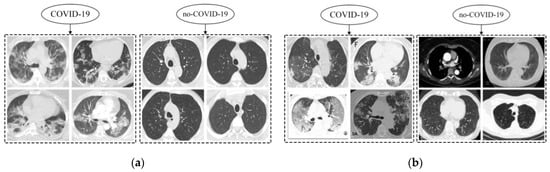

3.2. Datasets